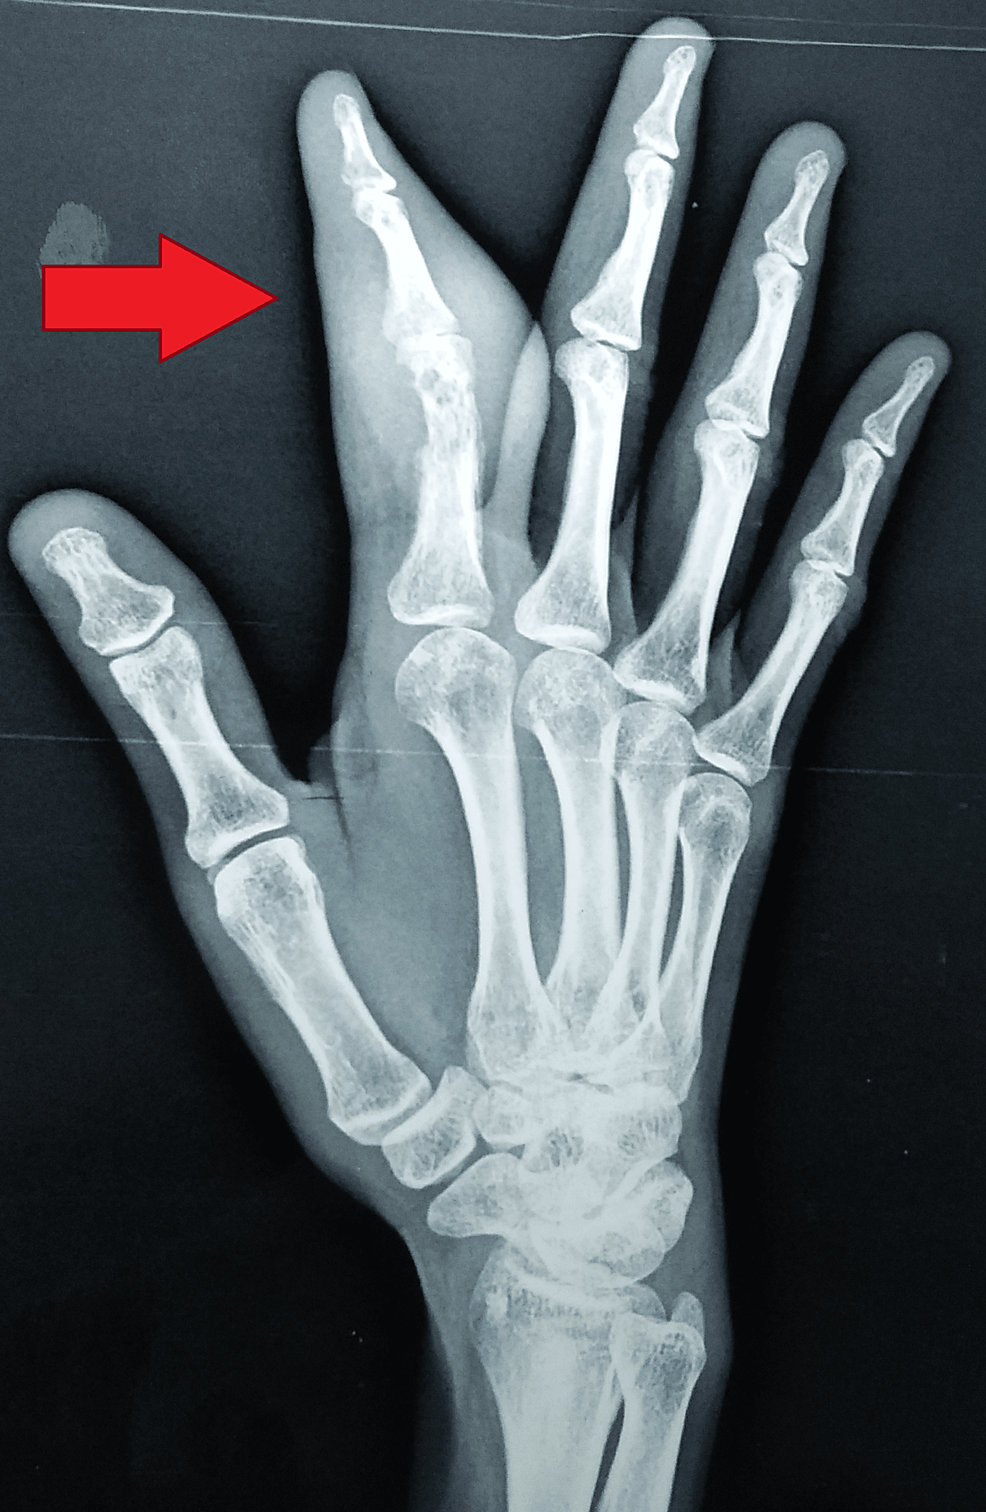

Radiograph of the right hand (PA view) showing soft tissue swelling Erosion Of Distal Phalanx lesions of the distal phalanx may arise secondary to benign or malignant pathologies and may reflect primary or. erosion of the distal phalanx. Many lcsions occur in the distal. Bakbara monsees and william a. 1) resorption of the terminal tuft (more. distal phalangeal erosive lesions. enchondromas are the most common primary bone tumour of the hand. Erosion Of Distal Phalanx.

AP radiograph of right thumb showing erosion of tip of distal phalanx Erosion Of Distal Phalanx Bakbara monsees and william a. lesions of the distal phalanx may arise secondary to benign or malignant pathologies and may reflect primary or. 1) resorption of the terminal tuft (more. Superficial acral fibromyxoma of the toe, with erosion of the distal phalanx. distal phalangeal erosive lesions. erosion of the distal phalanx. enchondromas are the most common. Erosion Of Distal Phalanx.